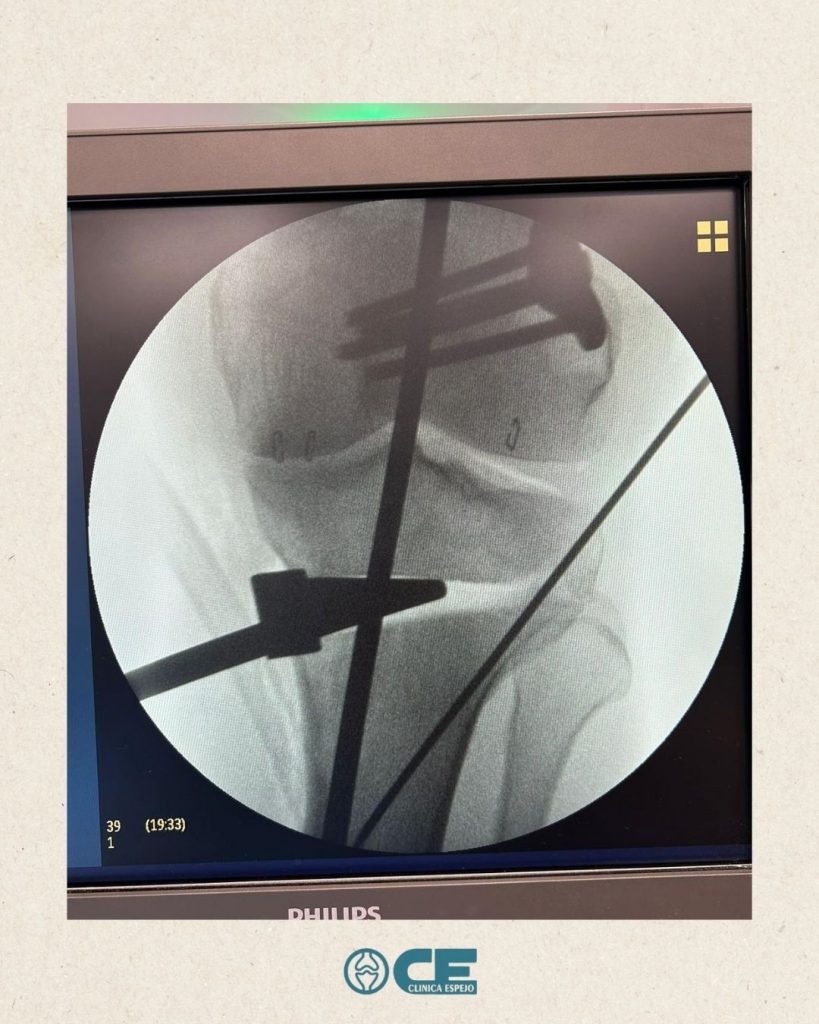

- 🏥El pasado martes nos visitó el Dr. Rusiecki desde el Hospital Universitario Dr. Negrín (Las Palmas de Gran Canaria) de la mano de @newclip_iberia para asisitir a una sesión quirúrgica de osteotomías complejas en @vithas_hospitales

¡Esperamos que disfrutaras la jornada dura de trabajo!🙌🏼Editado